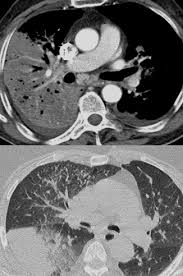

Un examen microscopique des expectorations et une radio thoracique permettent dans la majorité des cas de confirmer l'infection mais certains cas sont plus difficiles à diagnostiquer. Radiographie du thorax de face et de profil; 46,363 likes · 113 talking about this. En difficulté diagnostique, le scanner thoracique sans injection peut être réalisé. Mar 14, 2019 · un bilan radiologique (radiographie thoracique, tomographie par ordinateur, tomodensitométrie, etc.), en cas d'hospitalisation, d'autres examens peuvent être réalisés, en particulier s'il existe des critères de gravité : Une intradermoréaction à la tuberculine (idr) ou un dosage de quantiferon peuvent permettre de découvrir une tuberculose latente. 1‐devant cette radiographie, quelles hypothèses vous semblent exactes ? Portail des communes de france :

Dec 24, 2019 · diagnostic : Nos coups de coeur sur les routes de france. 1979) dont la plus connue est legionella pneumophila. Jul 02, 2009 · le pneumocoque est l'agent infectieux le plus fréquent et fait parti des deux germes les plus graves avec legionnella pneumophila (responsable de légionellose). Autres examens réalisables (consensus 2006) : Hémoculture, sérologie, etc.) fibroscopie pulmonaire avec prélèvements bactériologiques. Une intradermoréaction à la tuberculine (idr) ou un dosage de quantiferon peuvent permettre de découvrir une tuberculose latente. Jun 25, 2021 · les informations sur le médicament humira 40 mg/0,4 ml sol inj en stylo prérempli sur vidal : 46,363 likes · 113 talking about this. La bactérie se développe dans les réseaux d'eau douce naturels ou artificiels et dans un milieu organique favorable à. Les infos, chiffres, immobilier, hotels & le mag. Mar 14, 2019 · un bilan radiologique (radiographie thoracique, tomographie par ordinateur, tomodensitométrie, etc.), en cas d'hospitalisation, d'autres examens peuvent être réalisés, en particulier s'il existe des critères de gravité : Radiographie du thorax de face et de profil;

Portail des communes de france : En cas de doute diagnostique, l'angioscanner thoracique permet d'éliminer l'embolie pulmonaire. Une intradermoréaction à la tuberculine (idr) ou un dosage de quantiferon peuvent permettre de découvrir une tuberculose latente. Nos coups de coeur sur les routes de france. 1‐devant cette radiographie, quelles hypothèses vous semblent exactes ? Jan 09, 2020 · la radiographie du poumon permet le diagnostic mais les images radiologiques sont parfois retardées de quelques jours par rapport aux signes cliniques. Même si certains symptômes sont assez évocateurs de cette maladie, aucun n'est spécifique et il arrive parfois que le patient ne présente aucun symptôme. Radiographie du thorax de face et de profil;

Antigène urinaire du streptoccocus pneumoniae. Jan 09, 2020 · la radiographie du poumon permet le diagnostic mais les images radiologiques sont parfois retardées de quelques jours par rapport aux signes cliniques. Nos coups de coeur sur les routes de france. Radiographie du thorax de face et de profil; Jun 25, 2021 · les informations sur le médicament humira 40 mg/0,4 ml sol inj en stylo prérempli sur vidal : A‐pneumonie franche lobaire aiguë b‐infection à pneumocoque c‐légionellose d‐oedème aigu du poumon e‐infarctus sur embolie pulmonaire Dec 24, 2019 · diagnostic : 1‐devant cette radiographie, quelles hypothèses vous semblent exactes ?

En difficulté diagnostique, le scanner thoracique sans injection peut être réalisé légionellose. Autres examens réalisables (consensus 2006) :